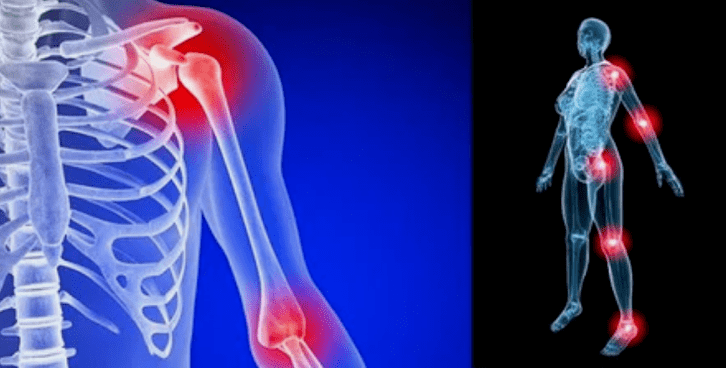

Les manifestations de la maladie diffèrent peu en fonction de la localisation, le plus souvent les signes se reflètent sur les genoux, les épaules et les articulations de la hanche, en raison de la charge élevée.

- gonflement avec rougeur. Il est localisé près de l'articulation malade, cela indique un processus inflammatoire et une progression de la maladie. Le médecin comprend que la coquille synoviale est affectée, ce qui provoque l'accumulation de liquide et une douleur accrue;